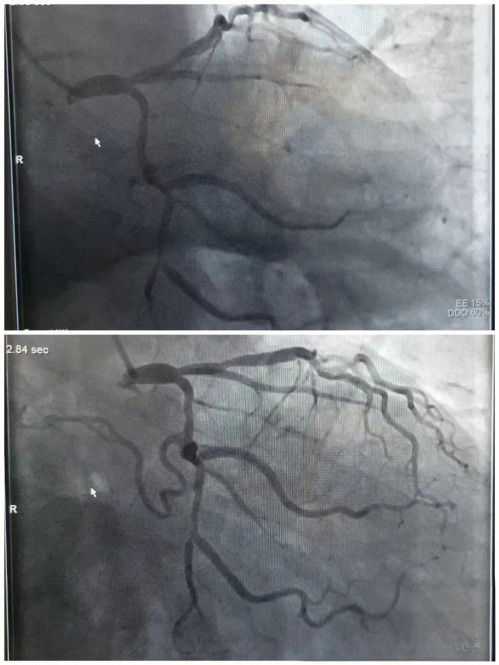

他们穿上重达十几斤的铅衣,关键的诊断性手术——急性冠状动脉造影术随机开始,当清晰的影像在屏幕上亮起,堵塞的血管被成功定位时,心内科介入团队明白,此时必须立即进行PCI手术开通血管。

诊断明确后,真正的攻坚战旋即展开。导丝、球囊、血栓抽吸、支架......一系列操作在团队的默契配合下有条不紊。随着堵塞的血管成功开通,患者濒死般的胸痛症状迅速缓解,生命体征也随之转危为安。